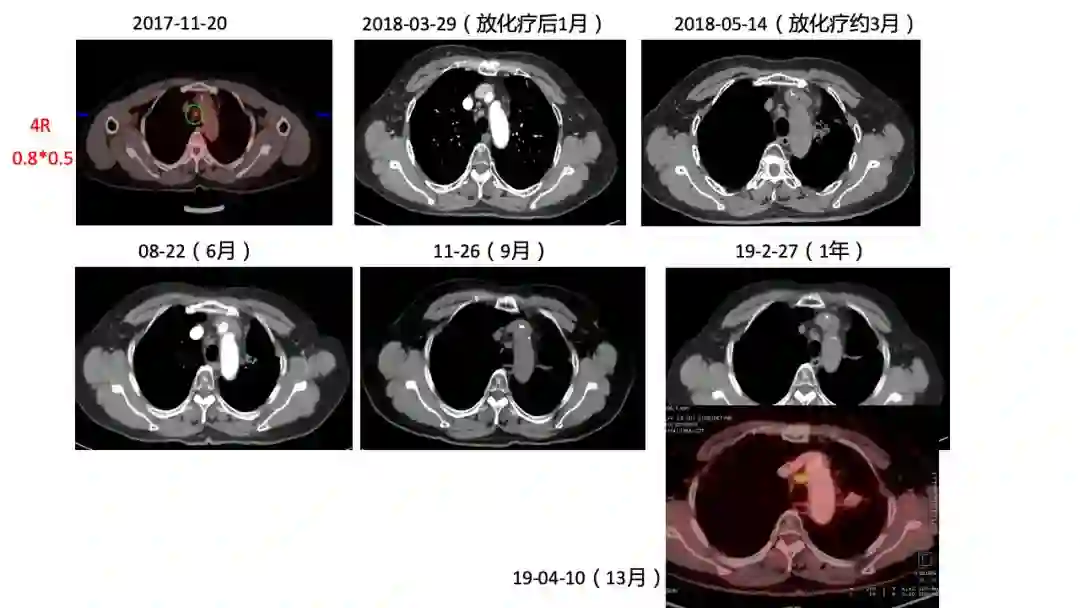

2)患者2017年11月因晨起咯血丝痰在外院行CT提示肺部肿物,考虑肺癌,后于2017-11-20我院行PET-CT,提示左肺下叶肿块,纵隔8L组淋巴结肿大,糖代谢增高,考虑左肺下叶中央型肺癌并纵隔淋巴结转移;左肺下叶阻塞性炎症。

2018-01-11开始行同步放化疗,放疗予以IMRT 60Gy/30F,化疗予以EP方案同步2周期。

2)诊断:左下肺小细胞肺癌cT2bN2M1 IV期  PFS=12月。

3)原发灶+8组LN(放疗区) PR 疗效。

5)4R,10R组LN(非放疗区)1年来随访大小未见变化,4R实性程度增高,代谢增高2倍。

初诊时4R,10R LN增大,PET考虑炎症,未行放疗,随访期间淋巴结大小无变化,NSE稳定正常,建议观察,3个月后复查CT。